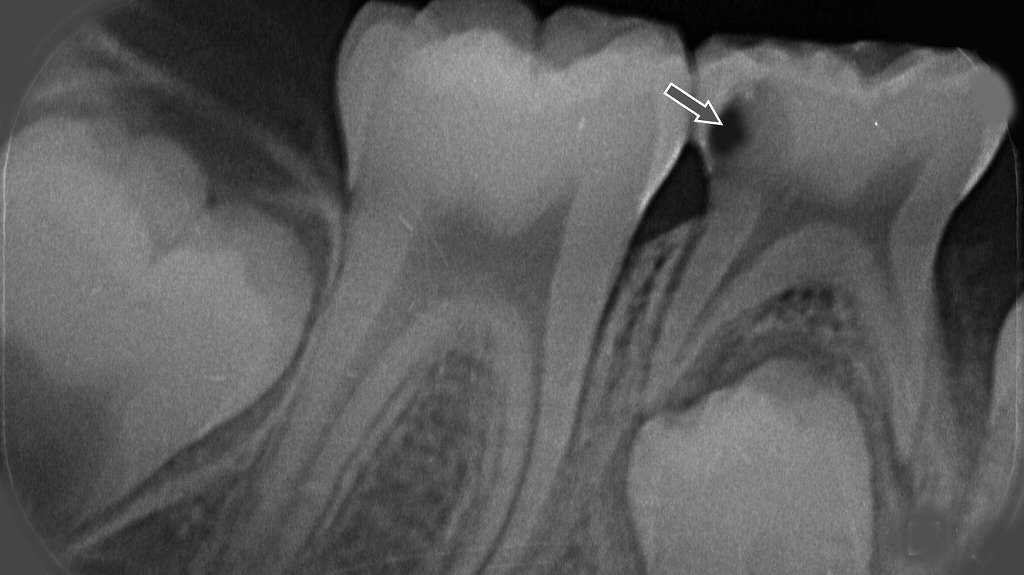

乳歯のC3虫歯

乳歯の遠心面にC3まで進行した深い虫歯(矢印部)。神経まで虫歯が達しており、抜髄が必要な状態を示すX線画像。